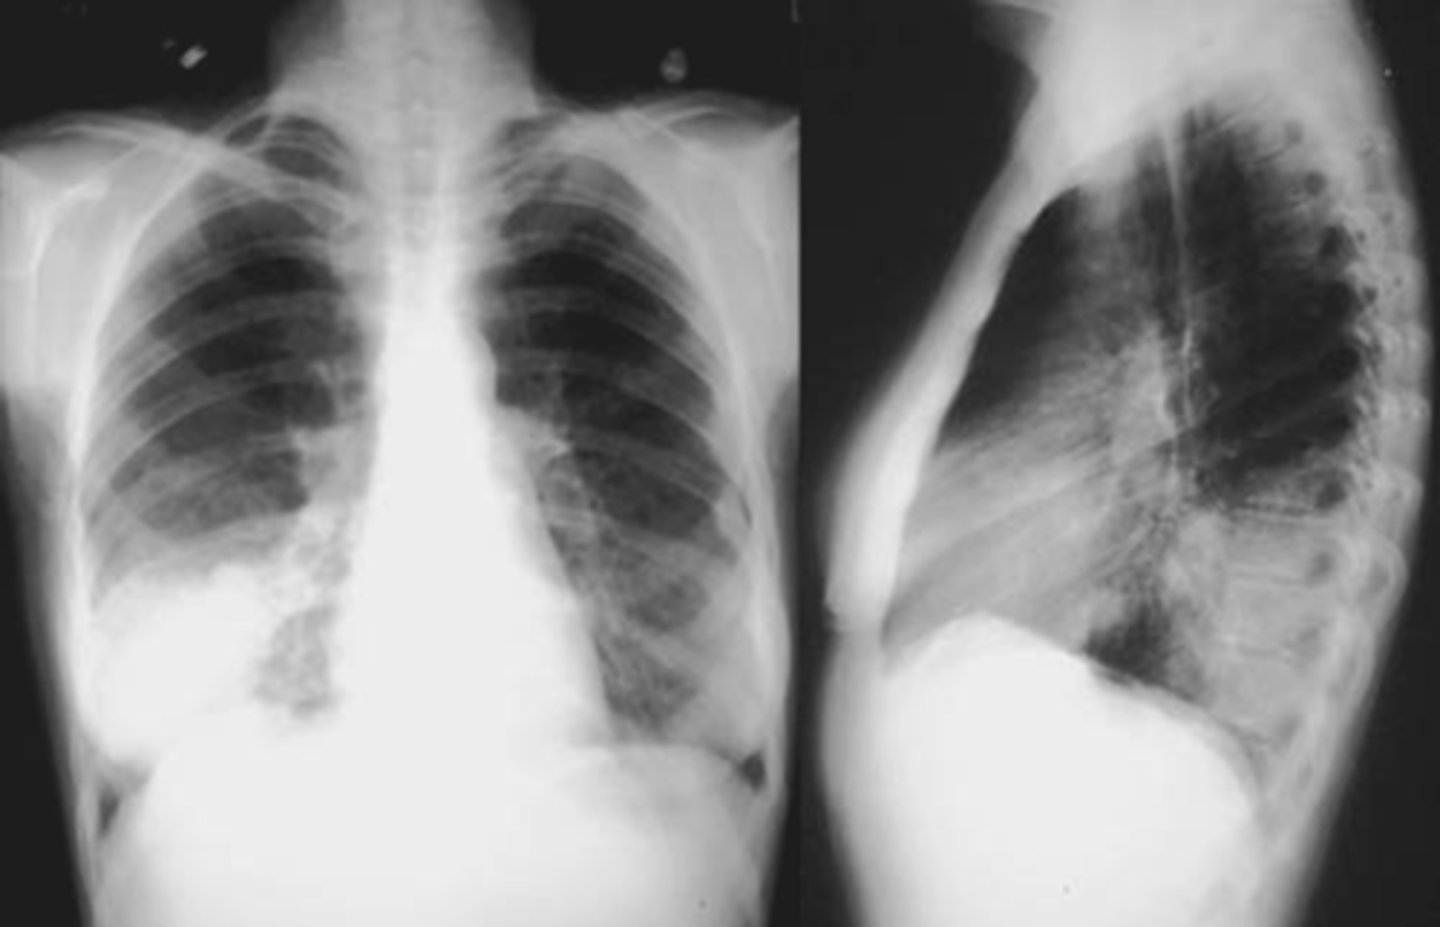

CAP- interstitial

CAP- round